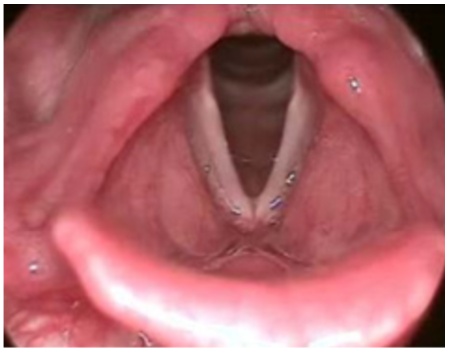

There are not many universal, unequivocal truths in medicine, but we can mostly agree that breathing is pretty important. It follows that diseases, injuries, or illnesses that interfere with our airways are problematic. Hereditary angioedema is a uniquely terrifying pathology in which the body’s inflammatory system is aberrantly activated, leading to swelling and collapse of a patient’s larynx. In this case, Dr. Shaw walks us through a presentation and management of a patient with hereditary angioedema in the emergency department.